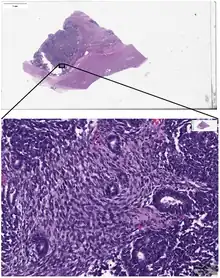

_stain_of_mixed_malignant_germ_cell_tumor_-_crop.png.webp)

Digital pathology has been approved by the FDA for primary diagnosis.[9] The approval was based on a multi-center study of 1,992 cases in which whole-slide imaging (WSI) was shown to be non-inferior to microscopy across a wide range of surgical pathology specimens, sample types and stains.[10] While there are advantages to WSI when creating digital data from glass slides, when it comes to real-time telepathology applications, WSI is not a strong choice for discussion and collaboration between multiple remote pathologists.[11] Furthermore, unlike digital radiology where the elimination of film made return on investment (ROI) clear, the ROI on digital pathology equipment is less obvious. The strongest ROI justification includes improved quality of healthcare, increased efficiency for pathologists, and reduced costs in handling glass slides.[12]

{{cite conference}}: CS1 maint: multiple names: authors list (link) - ↑ Lourenço BC, Guimarães-Teixeira C, Flores BCT, Miranda-Gonçalves V, Guimarães R, Cantante M; et al. (2022). "Ki67 and LSD1 Expression in Testicular Germ Cell Tumors Is Not Associated with Patient Outcome: Investigation Using a Digital Pathology Algorithm". Life. 12 (2): 264. doi:10.3390/life12020264. PMC 8875543. PMID 35207551.

- Figure 2 - available via license: Creative Commons Attribution 4.0 International - ↑ "FDA allows marketing of first whole slide imaging system for digital pathology" (Press release). FDA. April 12, 2017. Retrieved May 24, 2017.